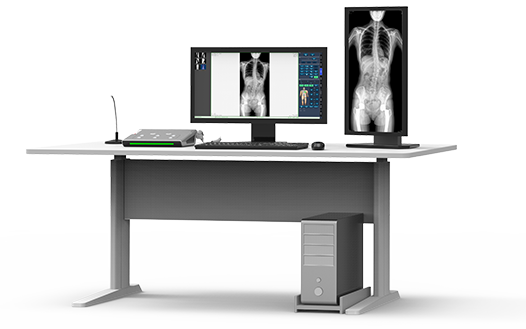

17"*34"有效視野,一次成像不拼接。相較于多張攝影再軟件拼接的DR設備,PLX8600解決了拼接圖像存在密度不均勻,拼接處圖像配準和放大效應等問題,給臨床帶來了大視野影像解決方案,可一次性覆蓋全脊柱或雙下肢影像。

除常規靜態攝影外,PLX8600大平板具備動態透視和點片功能,透視采集功能可支持大視野、多角度的可視化觀察。通過可視化的動態影像,配合點片功能,能夠很好的觀察復雜部位病灶,有效的抓取關鍵幀,降低患者多次攝片的概率。如:全脊柱狀態評估、長骨關節活動度、下肢靜脈造影瓣膜功能評估、消化道功能評估、脊髓造影等更多大視野臨床應用。